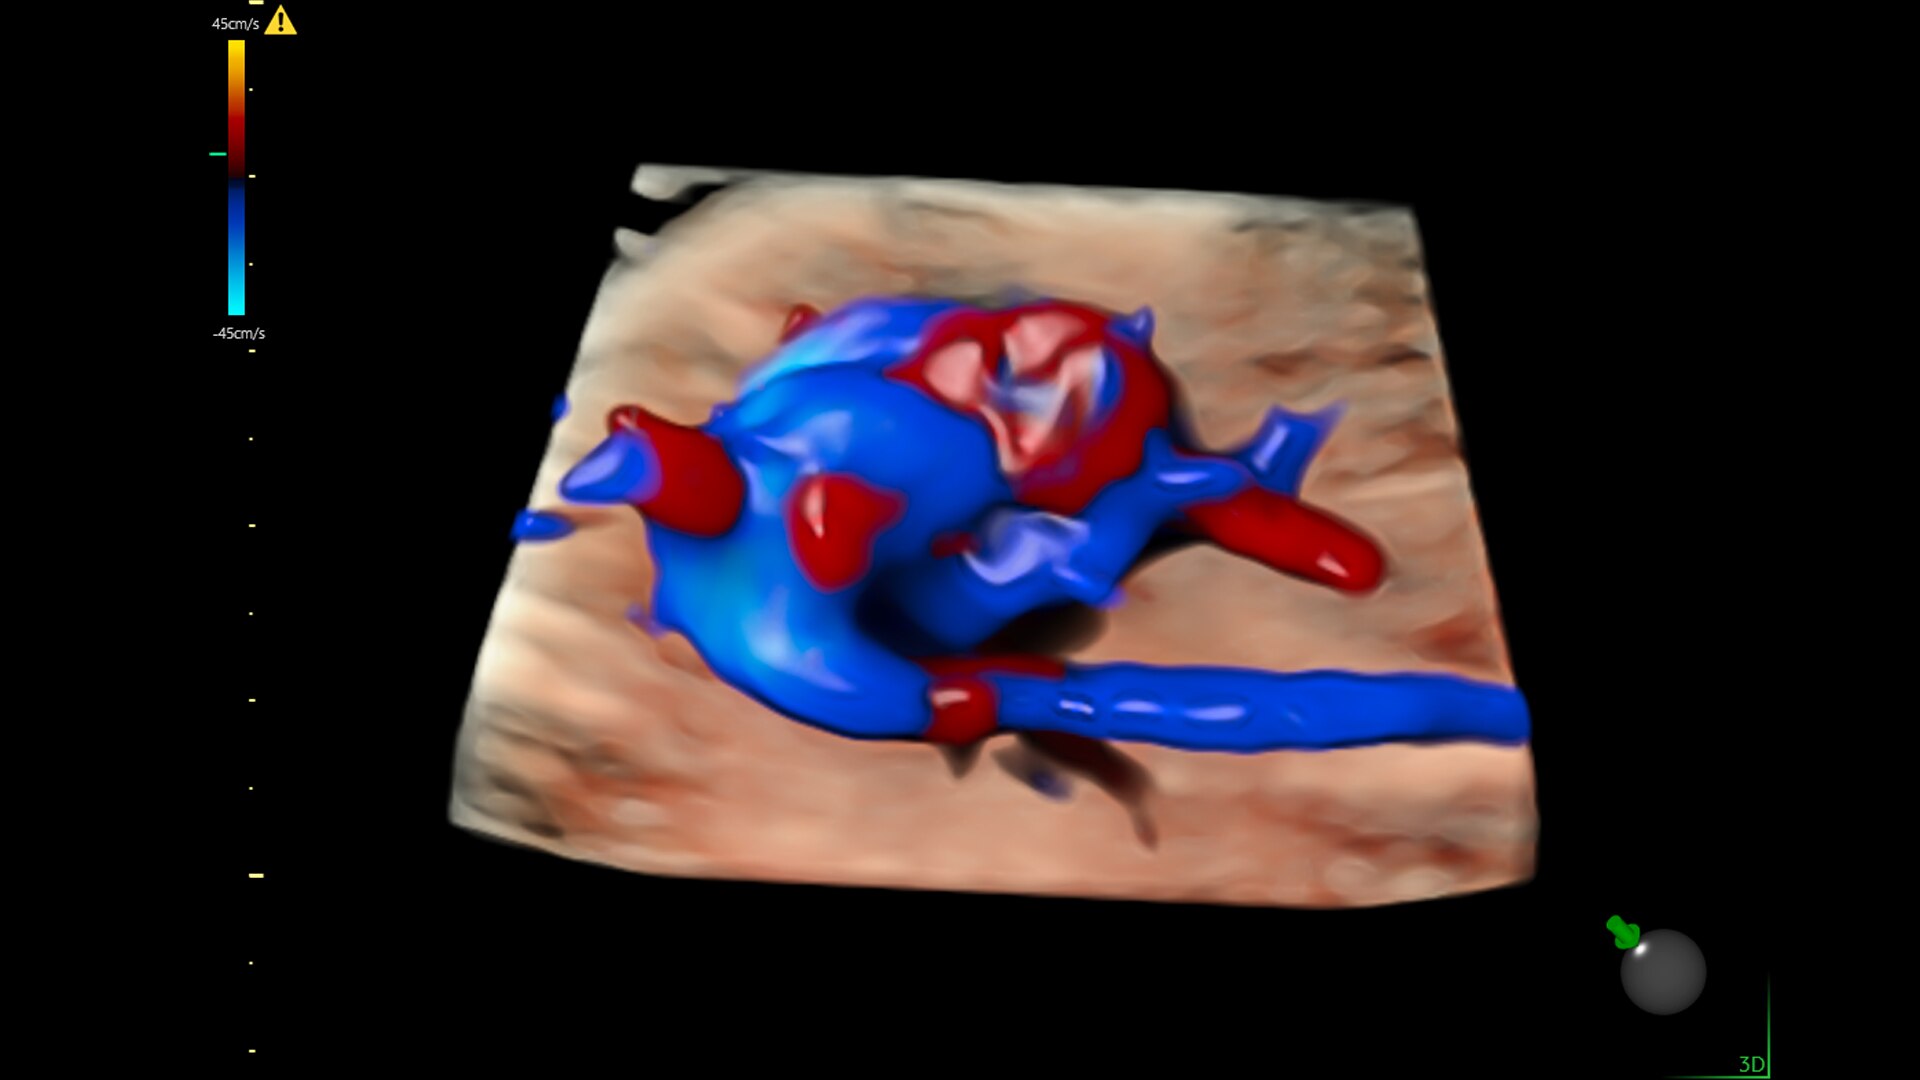

Fast, easy 3D-like blood flow visualization

Next level color Doppler that delivers exceptional sensitivity for easy, fast visualization of blood flow, displaying a 3D like appearance as seen in this 27-week fetal heart.

2-radiantflow-image